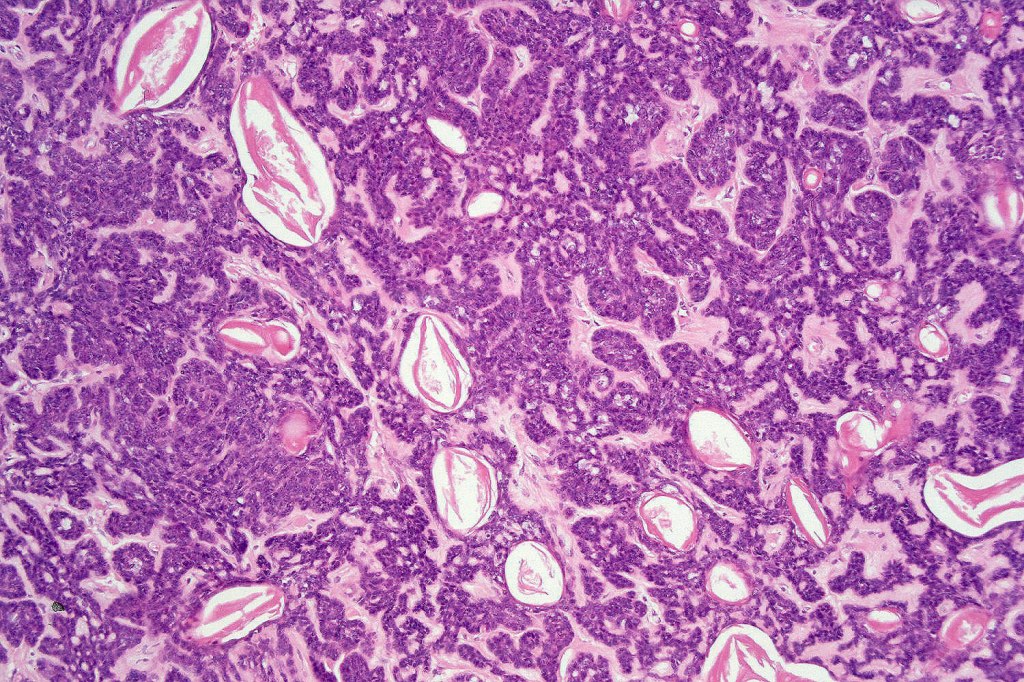

Histological features

•Variable continuity with epidermis

•Multinodular with surrounding collagenous stroma

•Random distribution of basaloid cells & sebocytes (<50% sebocytes)

•Duct formation, often with holocrine secretion generally present

•Mitoses sparse to conspicuous

•Absent peripheral palisading & retraction artifact

•Cystic variant

•Subtypes include rippled pattern, carcinoid-like & reticulated